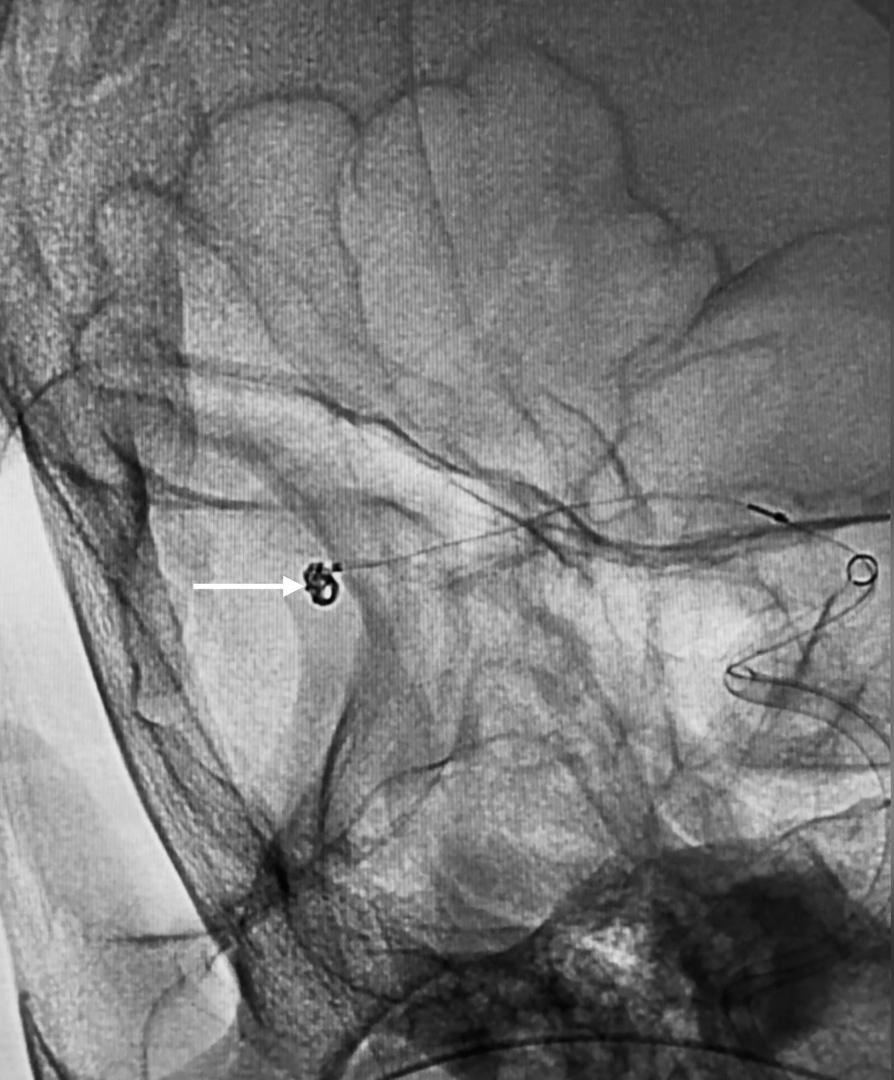

“Using a 1.7F microcatheter (with a diameter smaller than 1mm), the team carefully delivered a platinum coil 2mm in diameter and 4cm in length into the aneurysm sac.

“The coil was electrically detached once securely positioned, filling the aneurysm and preventing any further blood flow into it.

“Only the coil remains in the aneurysm, effectively neutralizing the risk of rupture,”

The statement also noted that the entire procedure was completed in 30 minutes, showcasing both technical precision and the capabilities of PCSH’s interventional radiology services.